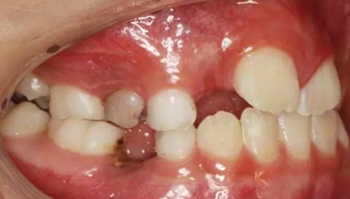

1、 患者 男 7歲 右下乳IV因齲早失